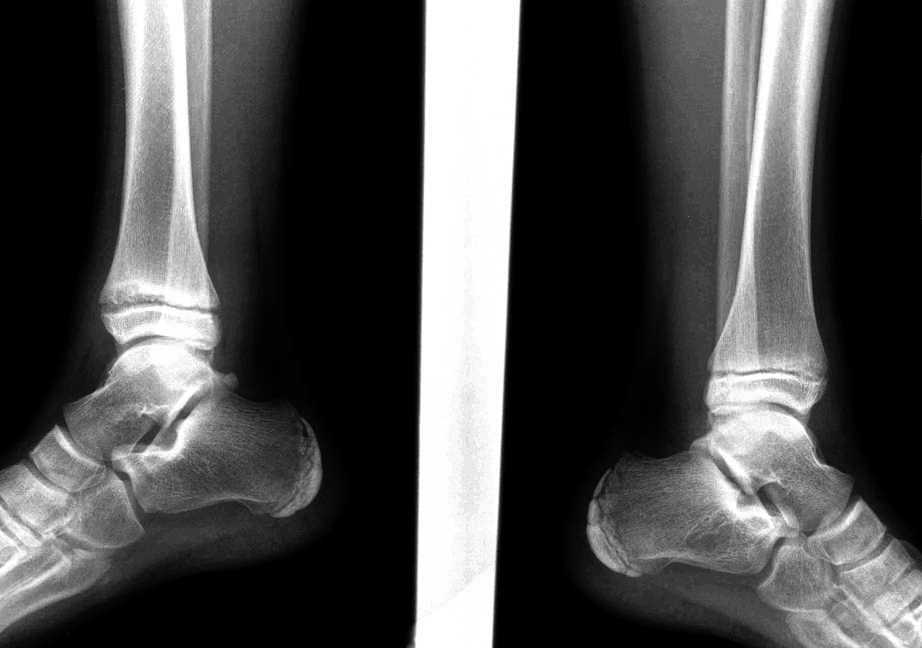

Остеоартроз левого(справа на снимке) голеностопного сустава

Для артрозов характерны такие изменения в голеностопном суставе:

- дегенерация хрящей и ухудшение их амортизирующей функции;

- асептическое воспаление и отек синовиальной оболочки;

- размягчение и изъязвление хрящей, обнажение подлежащих костей;

- субхондральный склероз костной ткани;

- сужение суставной щели и формирование костных экзостозов;

- гипотрофические и фиброзно-склеротические изменения параартикулярных тканей;

- прогрессирующая деформация сустава с нарушением его функций.